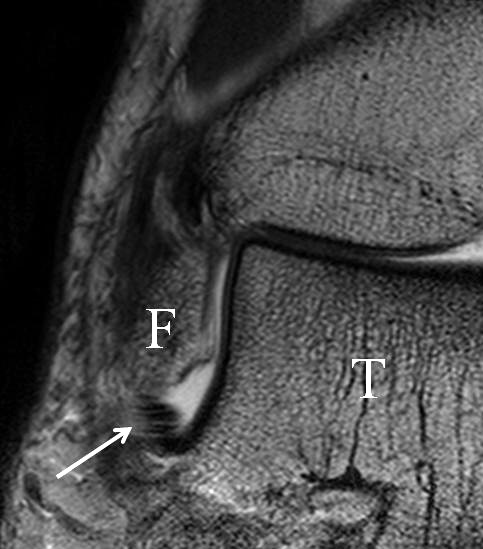

Innenbandapparat

Man unterscheidet bei dem Ligamentum deltoideum eine tiefe Schicht (Pars tibiotalare posterior, Pars tibiotalare anterius) und eine oberflächliche Schicht (Pars tibionaviculare, Pars tibiocalcaneare, Pars tibiotalare posterius superficialis und Tibiospring-Ligament) 10. Hochauflösende Techniken lassen eine differenzierte Beurteilung aller Bandanteile zu. Sowohl rein ligamentäre als auch osteo-ligamentäre Ausrisse sind normalerweise gut zu erkennen. Die Pars tibiotalaris posterior ist multifaszikulär aufgebaut und sowohl axial als auch coronar (Abb. 19 a) gut bildgebend abzugrenzen. Die deutlich kleinere, nur inkonstant angelegte Pars tibiotalare anterior inseriert an einem kleinen Talustuberkel (Abb. 19 b). Ossäre Bandausrisse kommen hier gehäuft vor. Proximal verlaufen die Pars tibiocalcaneare und die Pars tibionaviculare gemeinsam (Abb. 19 c) nach kaudal und trennen sich dann in zum Calcaneus und zum Os naviculare ziehende Bündel auf. Ein besonderer Typ ligamentärer Verbindungen stellt das Tibiospring-Ligament dar. Es verbindet nicht wie für Ligamente typisch zwei Knochen miteinander, sondern es hat seinen ossären Ursprung an der Tibia und inseriert am Pfannenband (Ligamentum calcaneonaviculare plantare, im englischen Schrifttum Spring-Ligament genannt), also nicht ossär. Das Innenband ist mit 60% der Verletzungen am häufigsten betroffen. Isolierte Innenbandverletzungen sind jedoch selten. Sie treten gehäuft assoziiert mit Syndesmosenläsionen, Fibulafrakturen, Verletzungen des Muskulus tibialis posterior und des Pfannenbandes auf (H.-K. Beyer 2003). Entsprechend sollte auf diese Kollateralverletzungen bei der Beurteilung geachtet werden. Eine weitere Folge von Verletzungen des Ligamentum deltoideum ist die chronische Sprunggelenksinstabilität. Arthroskopisch weisen hier bis zu 40% der Patienten einen elongierten Verlauf des Ligamentum deltoideum auf. In diesem Patientenkollektiv besteht auch eine erhöhte chondrale Komorbidität mit arthroskopisch erkennbaren Knorpelschäden (98%) im Gegensatz zu der Patientengruppe (66% Knorpelschäden) mit reiner Außenbandinstabilität 11. Dies belegt die klinische Bedeutung von Innenbandverletzungen.